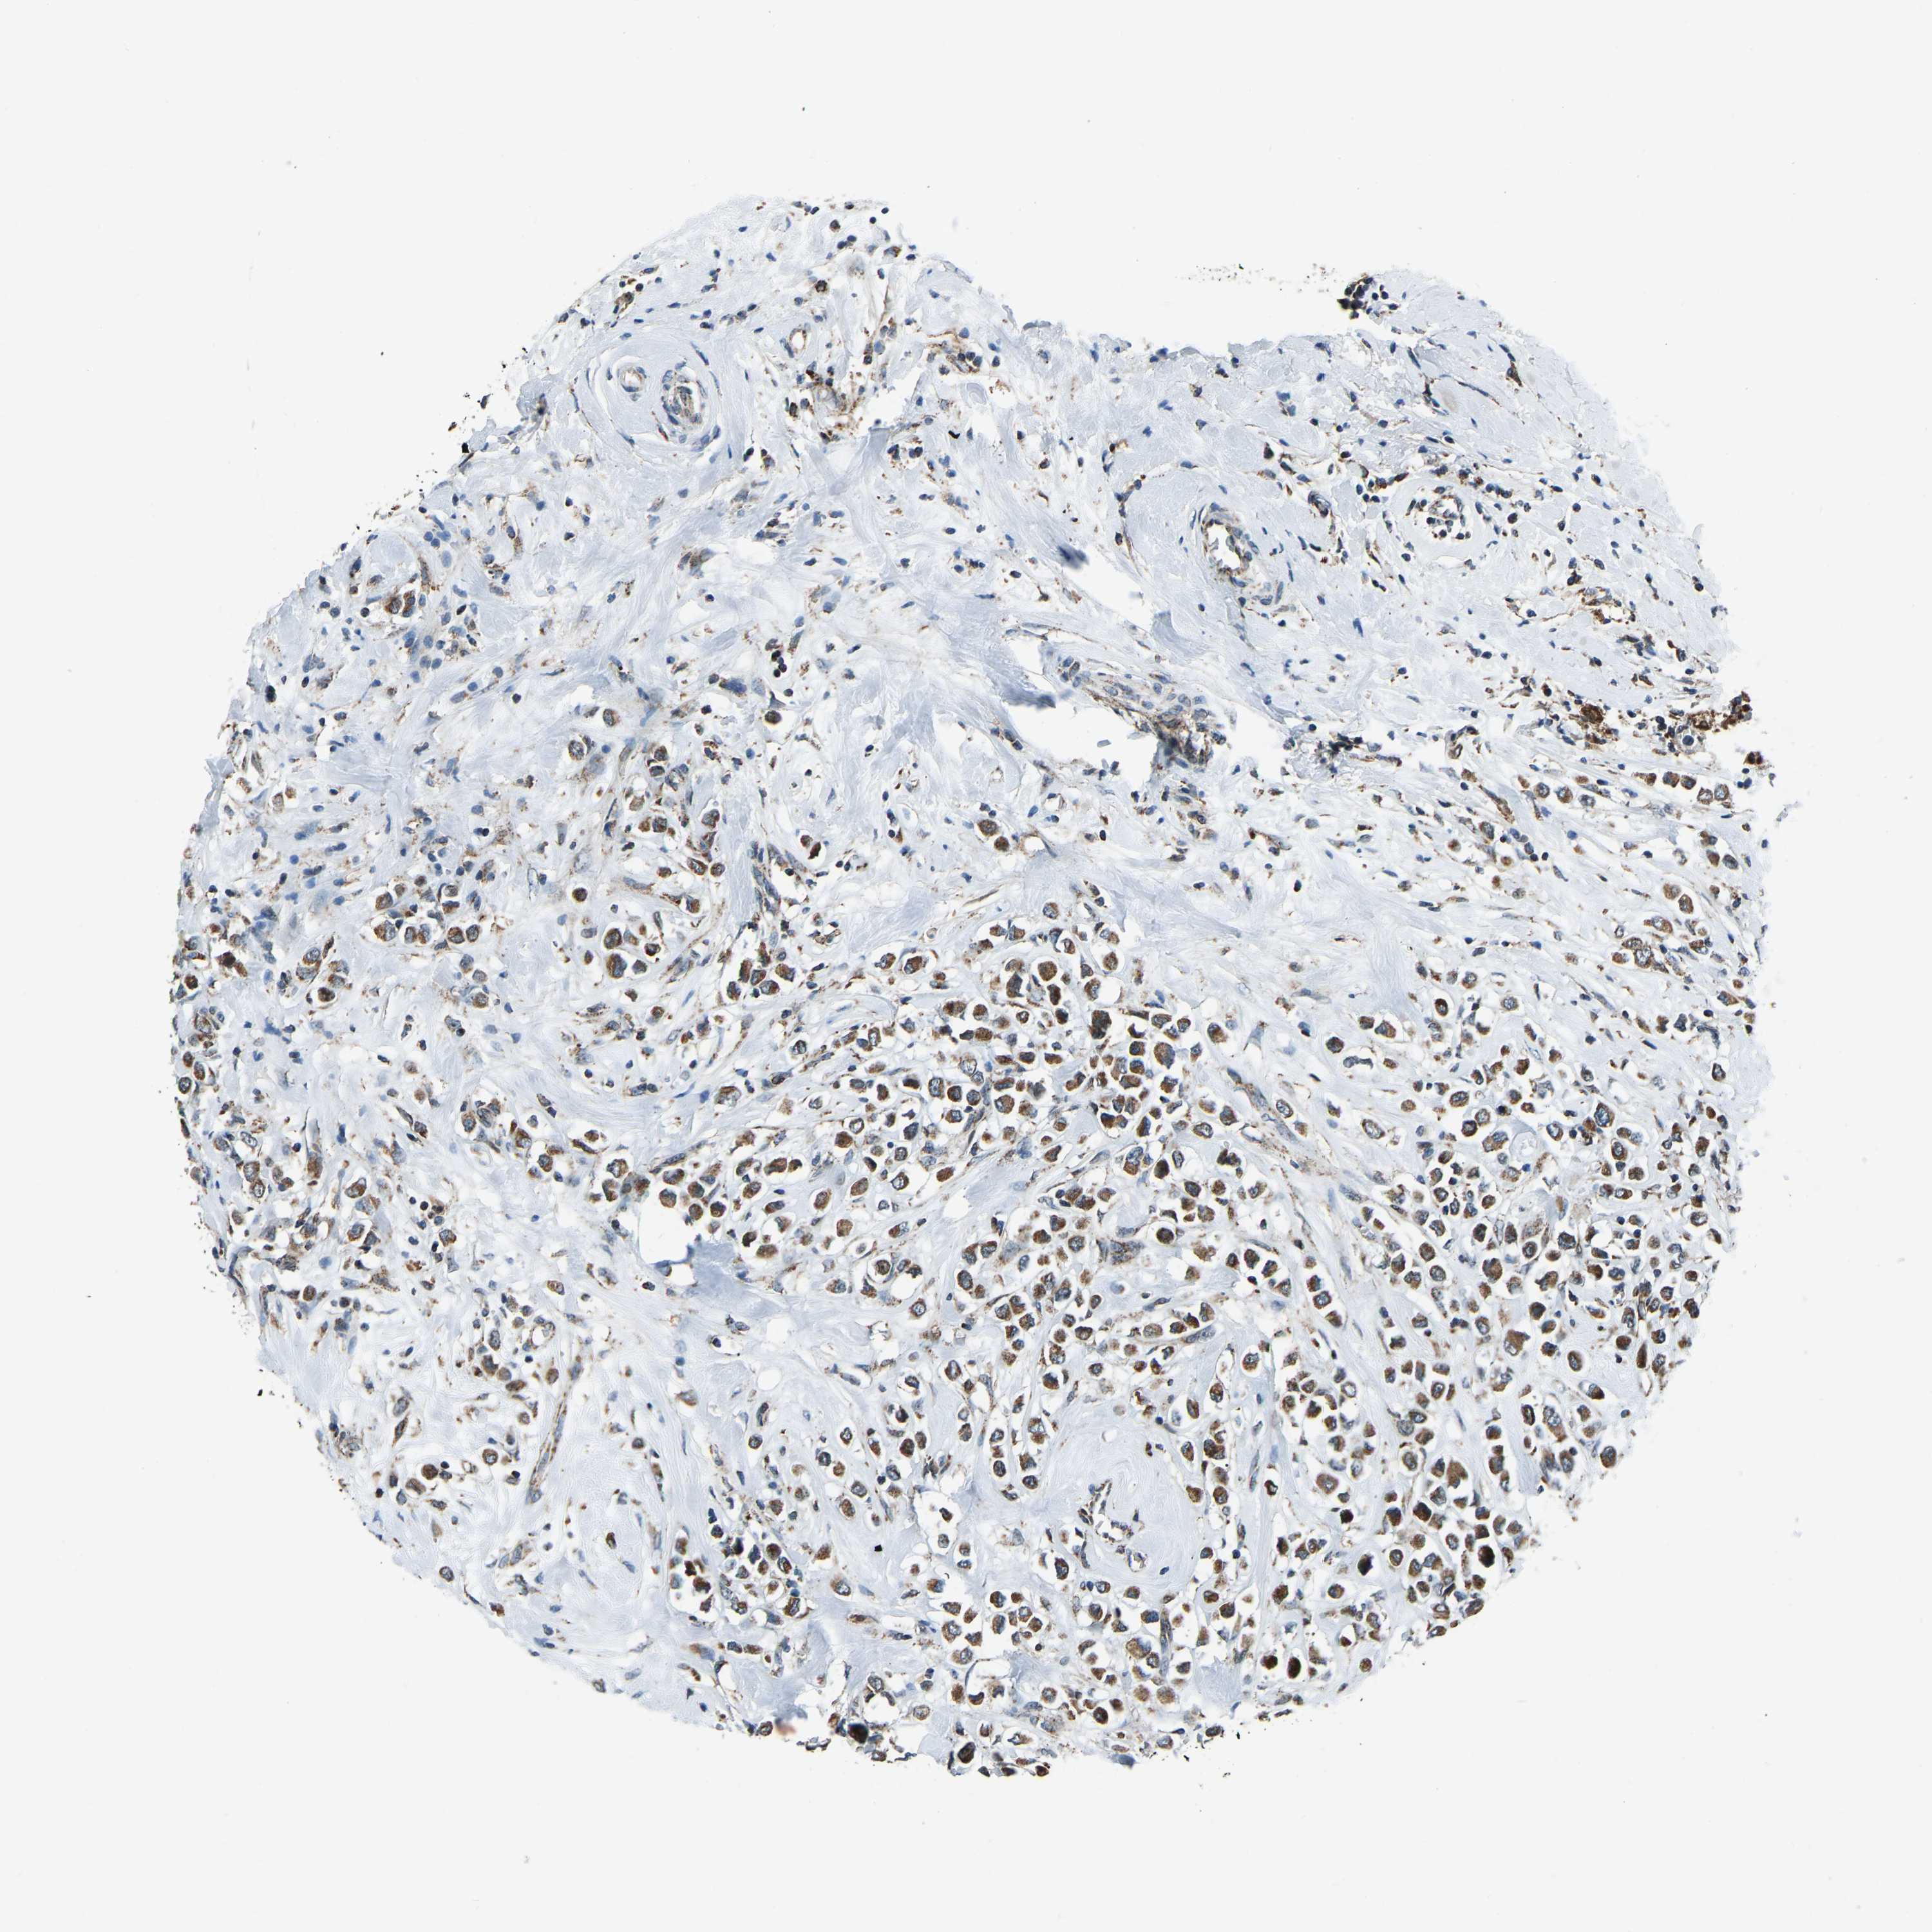

CANCER BREAST CANCER Show tissue menu

BRCA TCGA BRCA VALIDATION PROTEIN EXPRESSION